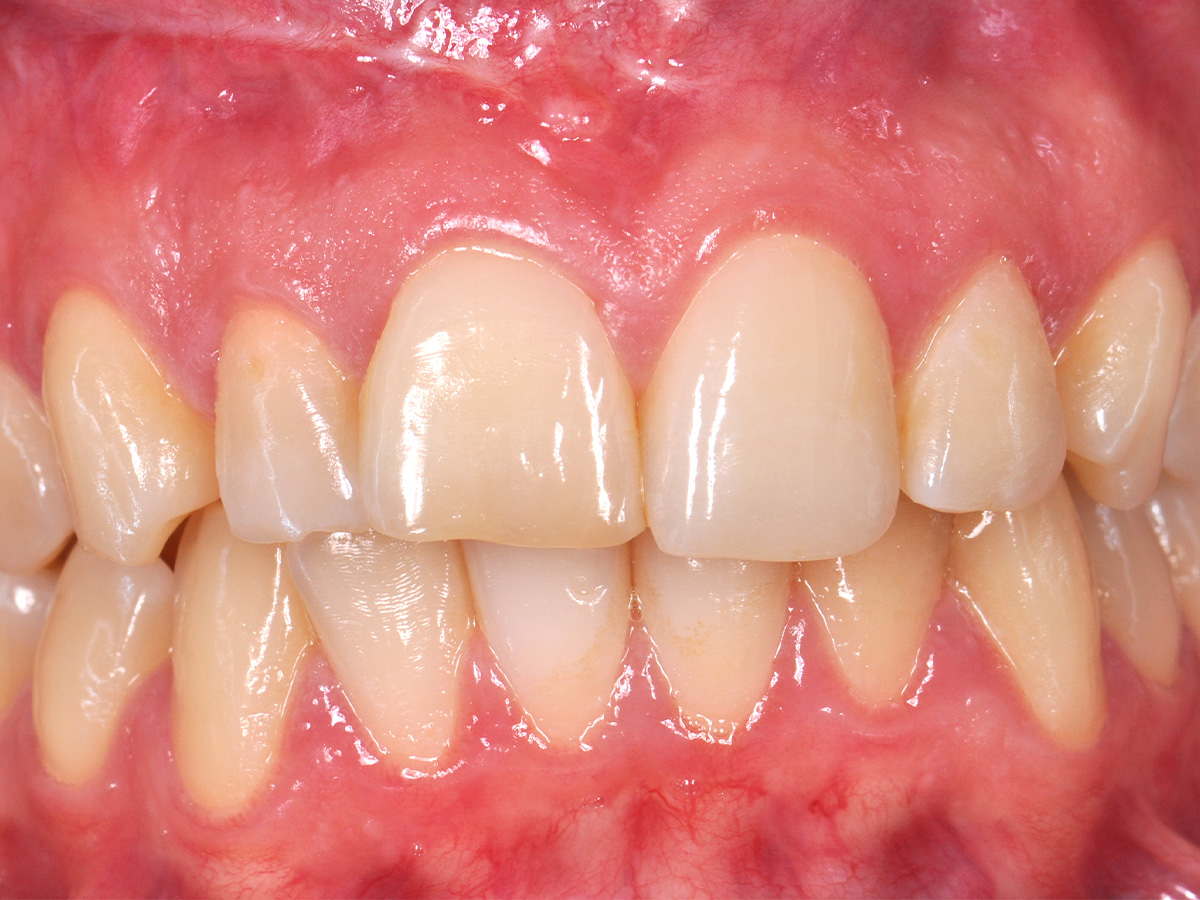

Abbildung 2

Prä-OP: Front nah en face.

Der postoperative Heilungsverlauf zeigte sich unauffällig. Die Nähte wurden am fünften postoperativen Tag bei reizlosen Wundverhältnissen entfernt. Die pathologische Zystenbalgbeurteilung bestätigte den klinischen Verdacht einer radikulären Zyste. Der Befund wurde nach drei, sechs und zwölf Monaten kontrolliert. Nach drei Monaten konnte keine Lockerung der Frontzähne mehr festgestellt werden. Die Narben zeigten sich blande, ästhetisch unauffällig und trotz der hohen Lachlinie gut unter der Oberlippe verborgen (Abb. 16). Die ossäre Durchbauung des gesamten Zystenbereichs erschien bei der radiologischen Verlaufskontrolle nach einem Jahr vollständig und solide (Abb. 17). Ein Zystenrezidiv konnte bislang klinisch und radiologisch ausgeschlossen werden. Sollten im weiteren Verlauf Zahn 11 und/oder Zahn 12 dennoch erneut Probleme entwickeln und entfernt werden müssen, besteht aufgrund er optimalen ossären Rekonstruktion die Möglichkeit, wiederum ohne die Weichgewebearchitektur zu stören, ein Sofortimplantat mit Sofortbelastung zu setzen und damit die soziale Ausfallzeit für die Patientin auf ein Minimum zu reduzieren. Bei stabilen Verhältnissen nach Operation wurde im Verlauf auf Wunsch der Patientin durch den weiter betreuenden Zahnarzt eine Veneer-Versorgung der Oberkieferfront zur vollständigen Wiederherstellung der ursprünglichen Zahnästhetik geplant.